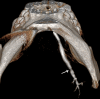

Methods: Patients with parotid or submandibular salivary symptoms were examined by 3D-CBCT sialography. They received an intraductal injection of 0.5 mL of water-soluble contrast medium maintained in the gland, followed by examination in a NewTom wide-field CBCT device. Images were processed with multiplanar and 3D reconstructions.

Results: A ductal exploration could be performed until the fourth divisions. The main lesions found were stones, stenosis, dilatations and "dead tree" appearance of the ductal system. No side effects of the catheterization or the iodine contrast were reported, nor tissue damages related to the contrast keeping technique.